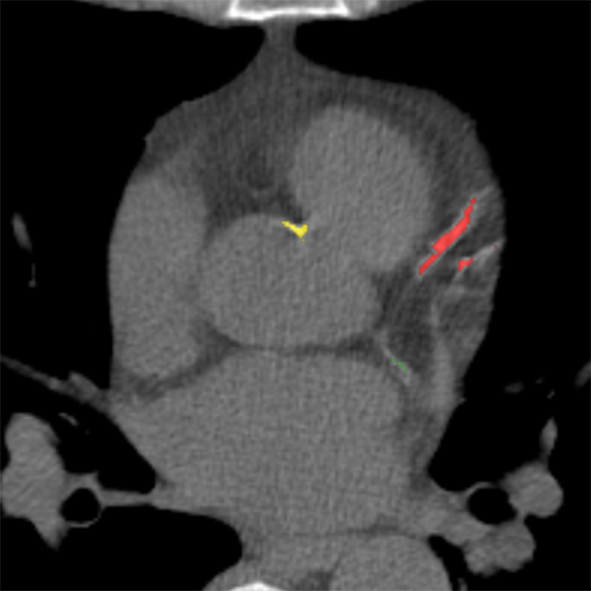

To establish a reference standard, calcifications were manually labeled in all scans. Scans were distributed among four trained observers and one radiologist with extensive experience in calcium scoring. To measure interobserver agreement, a subset of 100 scans (four scans from each of the 25 different scanner models and reconstruction algorithms) was annotated by two of the trained observers and the radiologist. Manual calcium annotation usually requires the observer to select only a single voxel per lesion. The lesion is then automatically segmented with region growing using the standard intensity threshold of . In low-dose scans, however, intensity based region growing often leads to large amounts of noise being segmented with the calcium (Figure 1). Moreover, it can lead to the spine and ribs being segmented together with calcium, or calcifications in arteries branching off the aorta being segmented together with calcium in the aorta. The observers therefore marked calcifications voxel-by-voxel () in the coronary arteries, the aorta and the aortic and mitral valves, including the annulus. Coronary calcifications were labeled as either left anterior descending artery (LAD), left circumflex artery (LCX) or right coronary artery (RCA). The left main coronary artery was considered part of LAD because these are difficult to distinguish on ungated scans. Motion artifacts caused by calcifications were annotated as calcifications because an exact separation of true calcification and artifact is often not possible. Depending on the amount of calcification and the image quality, the annotation effort varied from 5–10 minutes for images with soft reconstruction and little calcium to 60–90 minutes for images with sharp reconstruction and/or large amounts of calcium.

The performance of automatic CAC detection was evaluated based on scores per artery and per subject. Per artery and per subject sensitivities, average false positive volumes and F1 scores for CAC detection are listed in Table II. Examples of detected calcifications are shown in Figure 6.

(a)

(b)

(c)

(d)

(e)

(f)

(g)

(h)

(i)

(j)

(k)

(l)

For CAC and TAC detection, the method achieved a performance close to the level of interobserver agreement. The method was furthermore able to separate calcifications in the coronary arteries into LAD, LCX and RCA calcifications (Figure 6 (f)). The method as well as the observers were more successful in identification of LAD and RCA calcifications than LCX calcifications. The course of LCX is particularly difficult to follow in non-contrast scans. Hence, LCX calcifications can be difficult to differentiate from LM and LAD calcifications (Figure 6 (l)), as well as from those in the mitral valves. In comparison to CAC and TAC, calcifications of the aortic and mitral valves were less common in our dataset. Performance of the automatic method was below the performance of CAC and TAC detection. However, this is also a difficult task for experts. The observers especially disagreed on mitral valve calcifications, which is in line with findings of previous studies [45]. The disagreement is mainly caused by confusion with LCX calcifications and the lack of soft tissue contrast in the mitral valve region. For the aortic valve, confusion with TAC was the most common cause of disagreement.

False positive detections were mostly caused by mislabeling of calcifications with respect to their location (e.g., LAD and LCX), low-dose and motion artifacts, and other calcifications such as calcified lymph nodes or calcifications in other vessels (Figure 6 (i)–(k)). False positive detections outside the heart and the aorta occurred infrequently and usually in proximity to the heart or the aorta. This demonstrates that CNN1 was able to implicitly learn to recognize the typical spatial context of calcifications in the image. The individual evaluation of CNN1 additionally showed that CNN2 substantially contributes to reducing false-positive detections while maintaining a high sensitivity. However, future work could aim at unifying the two networks into a single network.

False negative detections were sometimes partially misclassified lesions (Figure 6 (h)–(i)). Partial misclassification can occur because the method performs voxel classification rather than the standardly used lesion classification. Even though voxel labeling occasionally causes partial misclassification of calcifications, it enables splitting of calcifications that are contained in more than one arterial bed, such as those partly located in the aorta and partly in the coronary arteries (Figure 6 (f)). Assigning a calcification that is partially contained in the aorta to the coronary artery could affect cardiovascular risk categorization. Similarly, assigning LM calcifications to the aorta would result in missing high risk lesions. To the best of our knowledge, this is the first method enabling splitting of the calcifications according to their arterial bed.